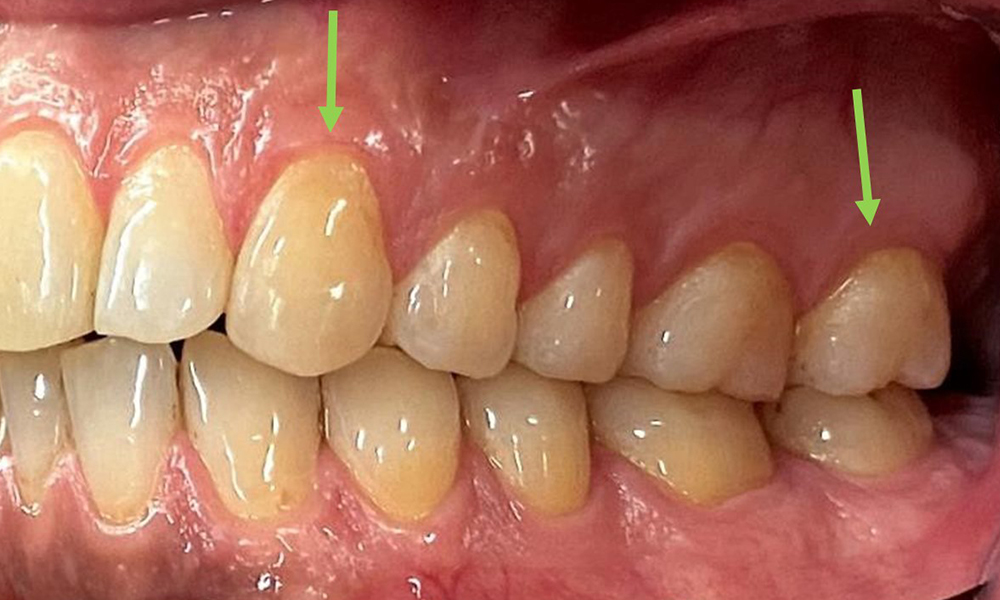

Extra- und Intraoraler Befund

Extraoral sind keine pathologischen Befunde festzustellen, intraoral zeigen sich bei der Frontalansicht im Bereich der keratinisierten Gingiva und am Übergang zur beweglichen Schleimhaut bräunlicheVerfärbungen (Abb. 2), welche auf den Nikotingenuss zurückzuführen sind. Am Gaumenbereich zeigen sich insbesondere im Bereich Oberkiefermolaren palatinal weißliche Schleimhautveränderungen, die ein Hinweis auf einen erhöhten Verhornungsgrad sind und ebenso auf den Nikotingenuss zurückzuführen sind. Die Zunge ist mit einem weiß-bräunlichen abwischbaren Belag versehen.

Die klinischen Sondierungstiefen liegen mit 1-3mm im physiologischen Bereich. Im Oberkiefer zeigen

sich von 13-16 sowie 23-27 Rezessionen bis 1mm. Der BOP liegt bei 15%.